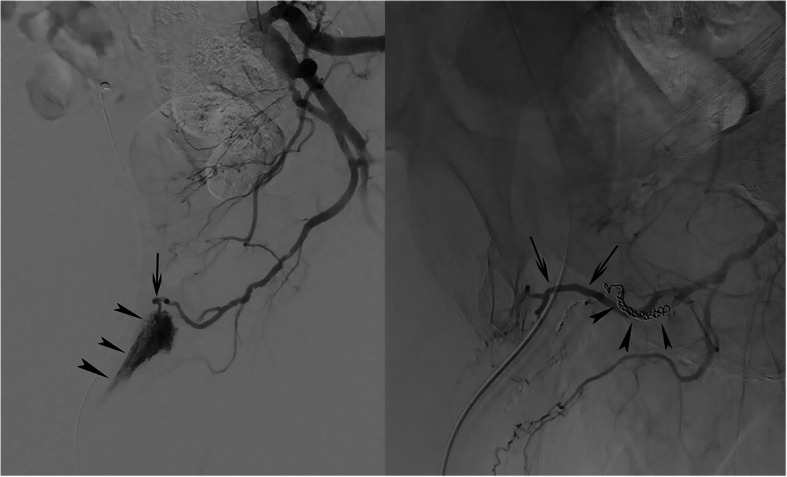

Case presentation: Two patients with a iatrogenic and non-iatrogenic urethral bleeding respectively are presented. Conservative management, including Foley catheter placement and endoscopic management were unsuccessful. Selective internal pudendal angiography revealed an arteriospongious fistula without clear contrast extravasation into the urethral lumen; super-selective embolization with microcoils and non-adhesive liquid embolics was safely performed and successfully stopped the bleeding. The postinterventional course was uneventful and both patients recovered without sequelae.

Conclusions: Traumatic urethral bleeding might be related to an arteriospongious fistula which can be successfully managed with super-selective coil and liquid embolic embolization.